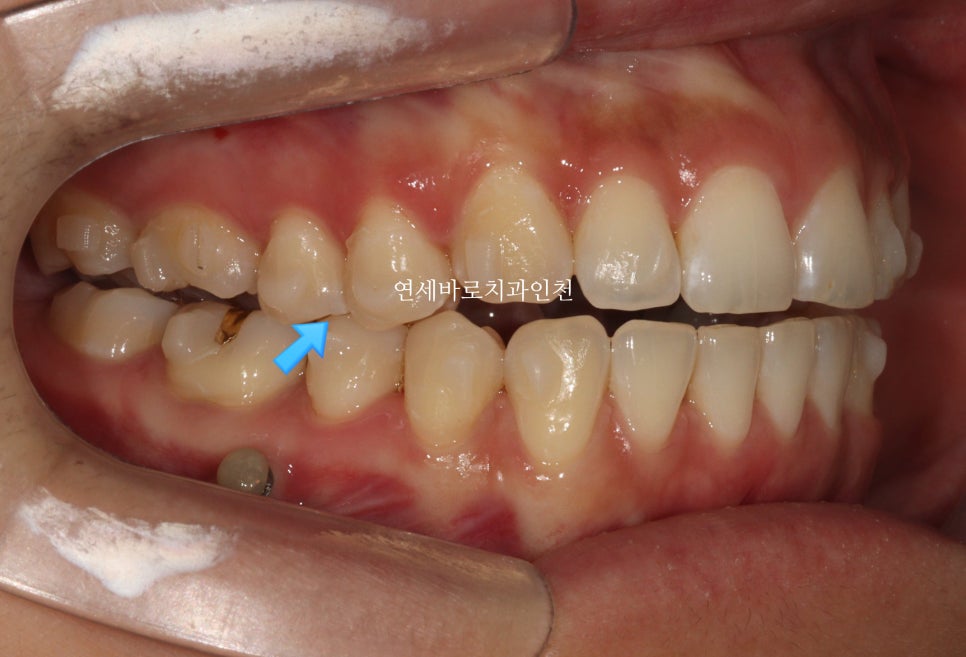

치료 초반의 모습입니다.

화살표 부분만 닿고 나머지는 다 닿지 않네요.

계획 그대로 진행되고 있는 겁니다.

무턱교정을 위해서는 위쪽 치아가 전체적으로 위쪽으로 올라가야합니다.

철사교정에서는 한덩어리로 잡고 한번에 올리지만

인비절라인에서는 다양한 옵션이 있는데, 이 환자분은 앞니, 그리고 어금니, 작은어금니를 나눠서 진행했습니다.

사진상 보이는 #미니스크류 도 사용하였습니다.

인비절라인 단독으로는 치료의 범위가 좁을 수 있지만, 미니스크류와 함께라면 조금 더 넓은 범위의 치료를 할 수 있습니다.